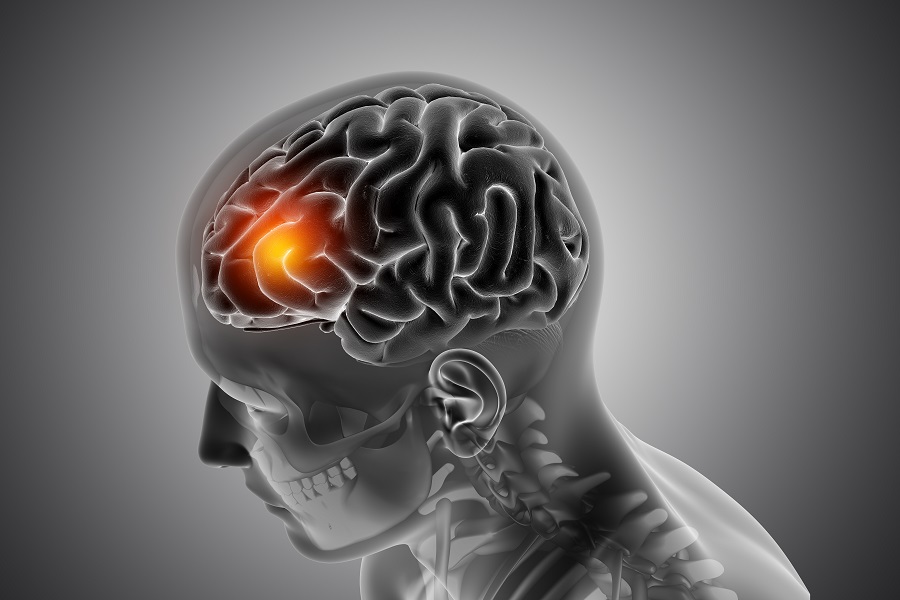

El accidente cerebrovascular (ACV) es una emergencia médica que puede cambiar la vida de una persona en cuestión de minutos. Ocurre cuando el flujo sanguíneo hacia una parte del cerebro se interrumpe o se reduce, provocando la muerte de millones de neuronas por falta de oxígeno y nutrientes. En un ACV, cada minuto cuenta: pueden llegar a morir hasta 1,9 millones de células cerebrales por minuto, por lo que la detección temprana y la atención médica inmediata son determinantes para evitar secuelas graves o incluso la muerte.